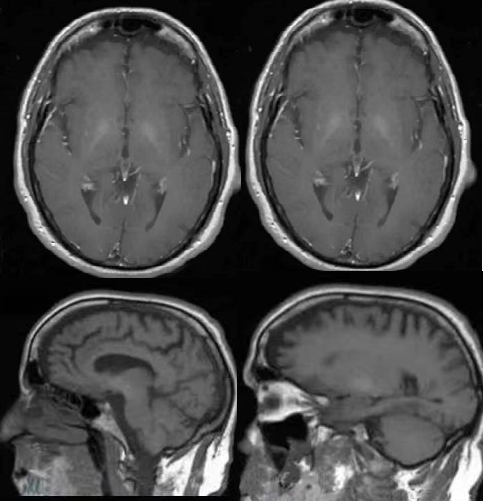

CASE 2

图 2 是另一例以震颤和精神异常为主要表现的慢性 HE,有肝硬化病史,MRI 可见轴位及矢状位 T1W1 双侧苍白球对称性高信号,增强后未见明显强化。